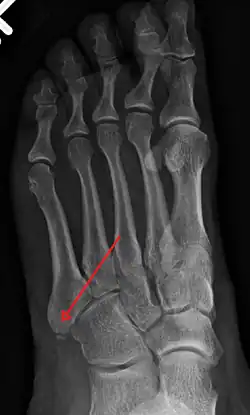

X-ray of foot.